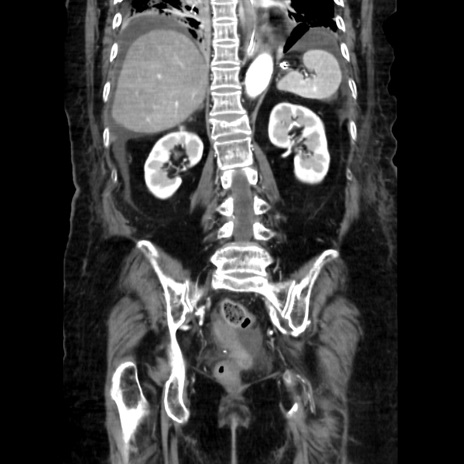

症例40(冠状断像)

【症例】90歳代女性

【主訴】腹痛・嘔吐

【現病歴】 食欲低下、嘔吐があり昨日他院受診。肺炎と診断され入院となる。入院後より腹部全体に圧痛あり。胃管留置され経過みていたが、症状持続するため、

当院転院となる。

【既往歴】胸椎圧迫骨折、胆石症

【身体所見】腹部:中央に激痛あり、圧痛あり、反跳痛不明

【データ】WBC 17100、CRP 18.82

冠状断像